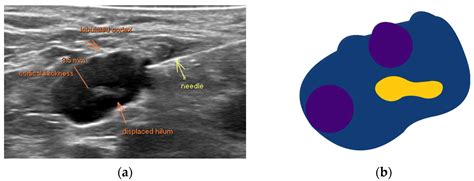

The functionality of the needle relies on suction - created either by a syringe attached to the needle hub or by hairlike action - to trace cellular textile into the lm of the needle. This sampling is then prepared on glass slide for cytological analysis. Because the technique retrieves cell preferably than solid tissue cores, it is exceptionally utile for appraise masses in areas such as the thyroid, salivary glands, lymph nodes, and chest.

• Lymph Node Assessment: Evaluate unexplained lymphadenopathy for signaling of infection, inflammation, or metastatic cancer.

• Deep-seated Lesions: When maneuver by ultrasound or CT imagination, the FNA biopsy needle can reach organ such as the pancreas or liver.

1. Formulation and Location: Using palpation or ultrasound counselling, the physician identifies the mark mass and cleans the skin surface with an antiseptic.

3. Needle Insertion: The FNA biopsy needle is inserted into the wound.

4. Ambition: If habituate a syringe, the plunger is draw back to make negative pressing. The needle is moved rearward and forth within the wound to dislodge cell.

Not all FNA biopsy needle models are indistinguishable. Selection depends on the body of the lesion and the depth of the prey. For highly vascularized lesion, smaller-gauge needles may be preferred to reduce hemorrhage risk, while slightly larger-gauge needle might be chosen for dense or fibrotic mickle to see adequate cell yield. Manufacturers now proffer specialized needle with echogenic tips, which raise visibility during ultrasound-guided procedures, farther increase the precision of the biopsy.